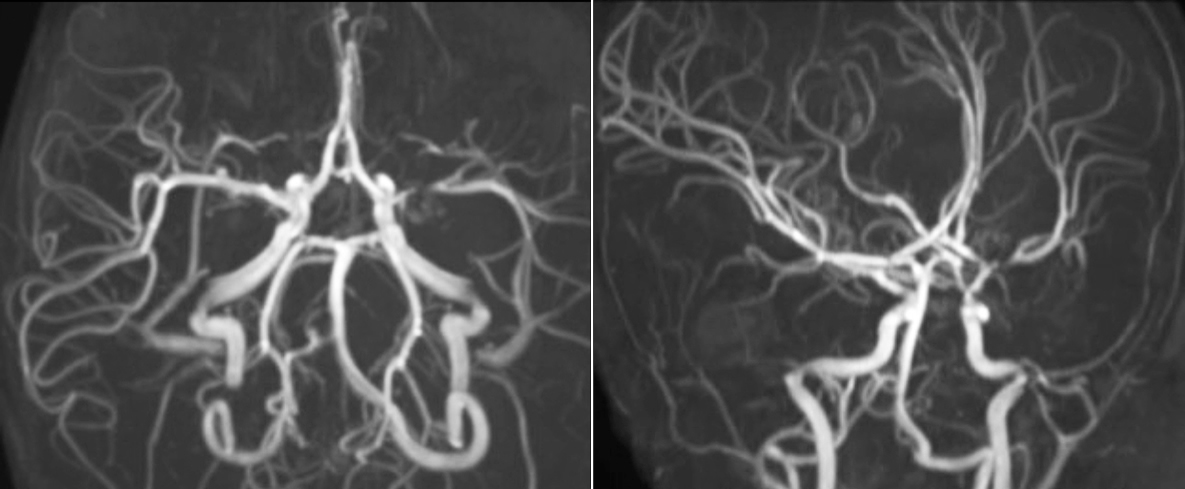

pCASL helps assess brain perfusion without contrast

Pseudo-continuous arterial spin labeling (pCASL) was developed for brain perfusion imaging without contrast agent. “This is very desirable in pediatric patients where the general trend is to limit the administration of contrast,” says Dr. Miller.

Dr. Miller uses pCASL for all patients who present with chronic and acute cerebrovascular abnormalities such as acute stroke, as well as patients who present with signs of acute inflammation in the brain, and occasionally in patients with tumors, to assess the perfusion status of their tumor.

“In combination with diffusion weighted imaging, it can help give a more extended assessment of the degree of perfusion abnormality in a patient who is suffering acute ischemia. We have a number of patients who have chronic arterial insufficiency due to prior arterial abnormalities or acquired arterial abnormalities such as sickle cell disease or neurofibromatosis. Sometimes the child’s first manifestation of disease progression is a reduction in brain perfusion before stroke symptoms manifest clinically or in diffusion weighted imaging. We use pCASL to help delineate the perfusion abnormality.”

Growing confidence in specific applications

“We built up confidence in pCASL by comparing it to contrast-based perfusion imaging. Once we had confidence that it was representing what the contrast perfusions were representing, we increased our diagnostic confidence by serial imaging in either the acute stage or the long term stages in a number of patients with arterial abnormalities.

To other new users I would recommend to also start to interpret the pCASL images in comparison with other standard imaging – T2 and FLAIR and DWI – until the user gains confidence in interpreting these images by themselves.”

“A powerful use of pCASL is in patients with chronic cerebrovascular stenosis, where clinicians desire information on how compensatory mechanisms of the brain are performing to enable perfusion to the brain. Often clinicians take into account how the compensatory mechanisms appear to help to provide adequate perfusion to the patient’s brain, and they may intervene surgically or make some other management decision.”

“Another special application is the assessment of cerebrovascular reactivity with a Diamox perfusion exam, where we subtract two sets of pCASL images.”

Efficiencies gained with pCASL

“pCASL has now become more of a first-line scan for assessing perfusion for us, as opposed to DSC-based perfusion imaging with contrast agent. And in patients who were not planned to have contrast, we can perform pCASL for perfusion imaging without need to stop the exam, pull the patient out, and put in an IV. It also negates the postprocessing that’s necessary for dynamic susceptibility contrasts. And it allows us to repeat perfusion imaging in the same patient at the same imaging time, which is helpful in terms of patient motion, or in a situation where a scan needs to be done before pharmacological perfusion imaging.”